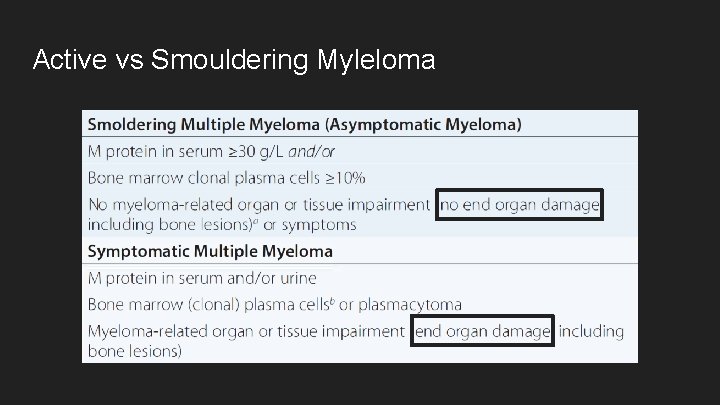

Active vs Smouldering Myleloma